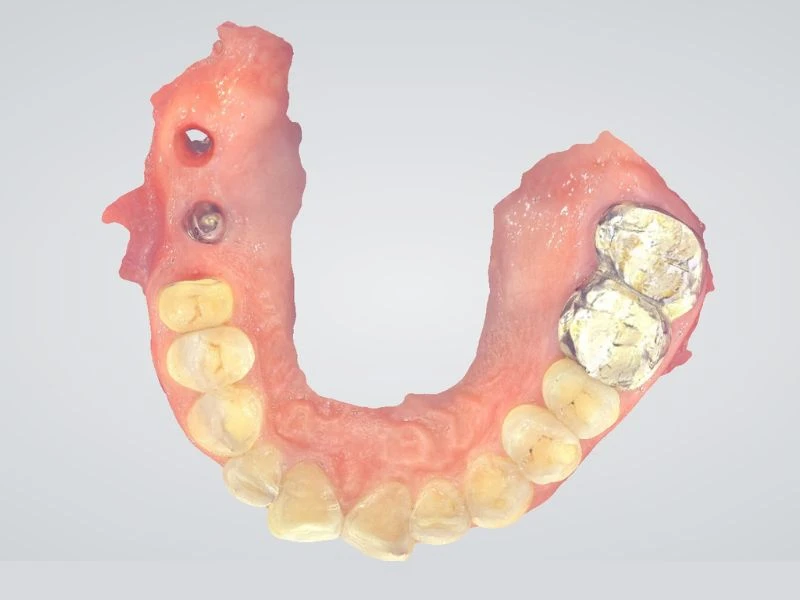

MÚI CHỊU

Múi răng khớp vào rãnh của răng đối diện được gọi là múi chịu. Múi trong của răng trên và múi ngoài của răng dưới được gọi là múi chịu.

MÚI CẮT

Múi ngoài của răng trên và múi trong của răng dưới được sử dụng để cắt thức ăn và được gọi là múi cắt.

Khớp cắn thăng bằng được cho là tồn tại khi có sự tiếp xúc đồng thời giữa các răng trên và răng dưới ở cả bên phải và bên trái, ở vùng răng trước lẫn răng sau khi hàm ở khớp cắn trung tâm.